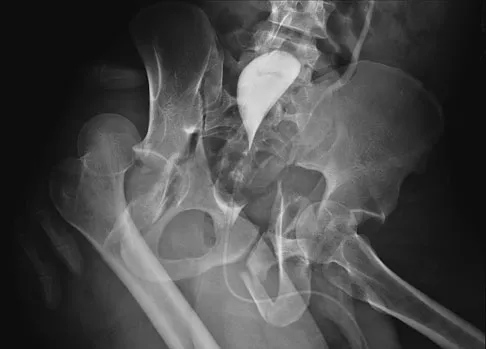

Figure 11 shows the radiograph of a 26-year-old man with type I diabetes mellitus who was struck by a motor vehicle. What is the most common complication associated with this pelvic fracture?

The most common complication following acetabular or pelvic ring injury is deep venous thrombosis (DVT). Without prophylaxis, rates of DVT are as high as 70% to 80%. With prophylaxis, the rates are around 10%. Infection rates in surgical repair of acetabular fractures are relatively low but a history of diabetes mellitus and a significant Morel-Lavalle lesion certainly increase the risk. However, even with these two complicating factors, the rates of infection are still lower than 10%. Sciatic nerve palsy rates from the injury alone approach 20% and iatrogenic injury is usually less than 2%. Degenerative changes to the hip following this injury approach 20% to 25%, even with an anatomic reduction. Geerts WH, Code KI, Jay RM, et al: A prospective study of venous thromboembolism after major trauma. N Engl J Med 1994;331:1601-1606.